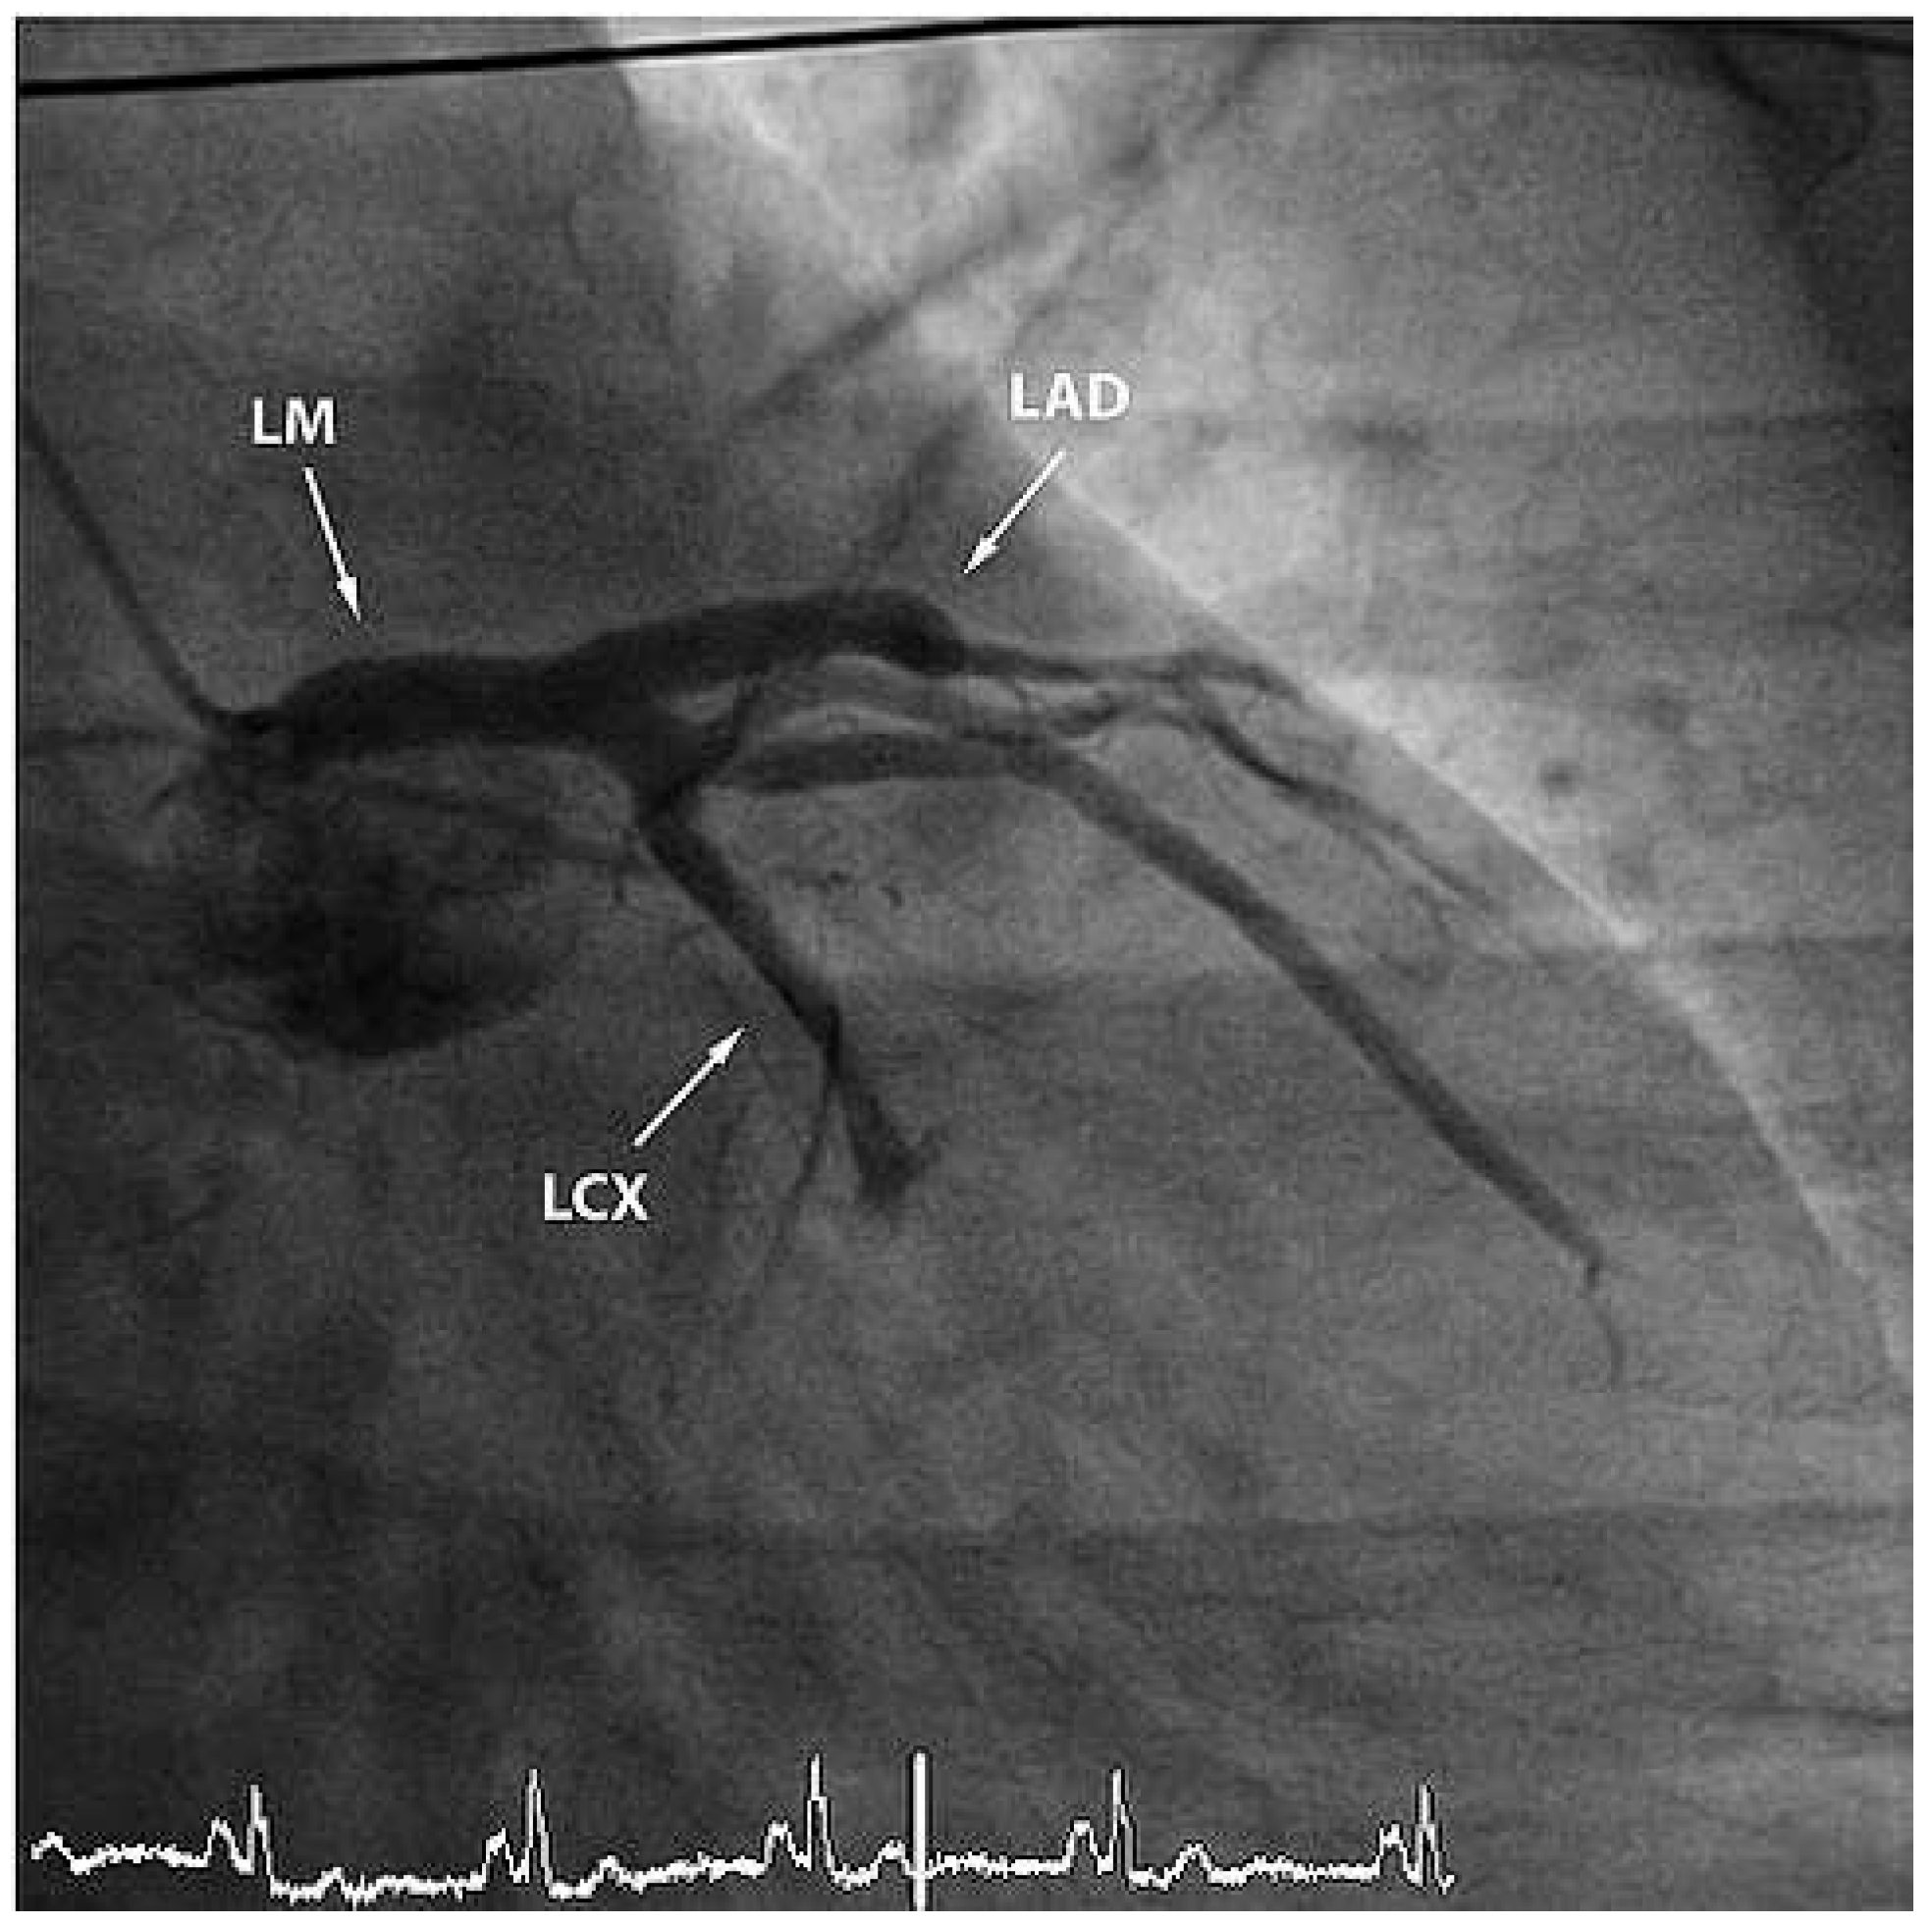

The ECG at admission showed normal sinus rhythm and ST-segment changes in the infero-lateral and the antero-septal leads (Figure 1). The initial troponin and CK-values were normal. Clinically the patient was in cardiogenic shock. Urgent invasive assessment revealed a severely depressed LV-function (EF 30%) with apical, anteroseptal and posterolateral akinesia. There was a total thrombotic occlusion of the mid LAD and the distal circumflex artery (Figure 2).

Figure 2. RAO view showing occlusion of the mid-LAD and of the left circumflex artery. LM = left main coronary artery; LAD = left anterior descending artery; LCX = left circumflex artery.